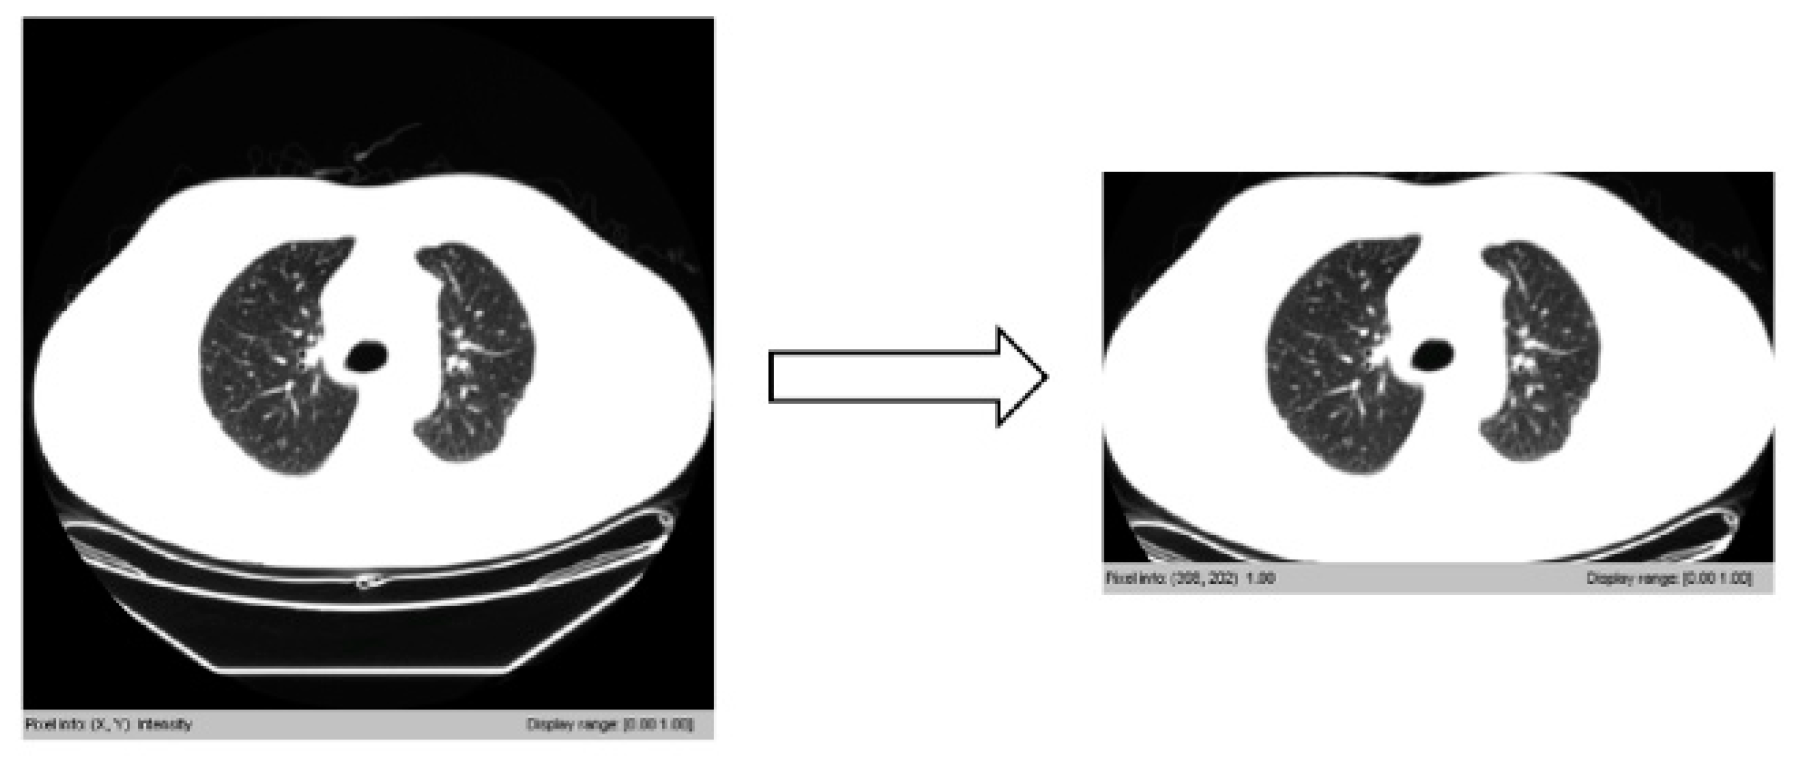

3.3.2. Removing Irrelevant Background Areas

3.3.3. Outlining the Lung Areas with a Box Field